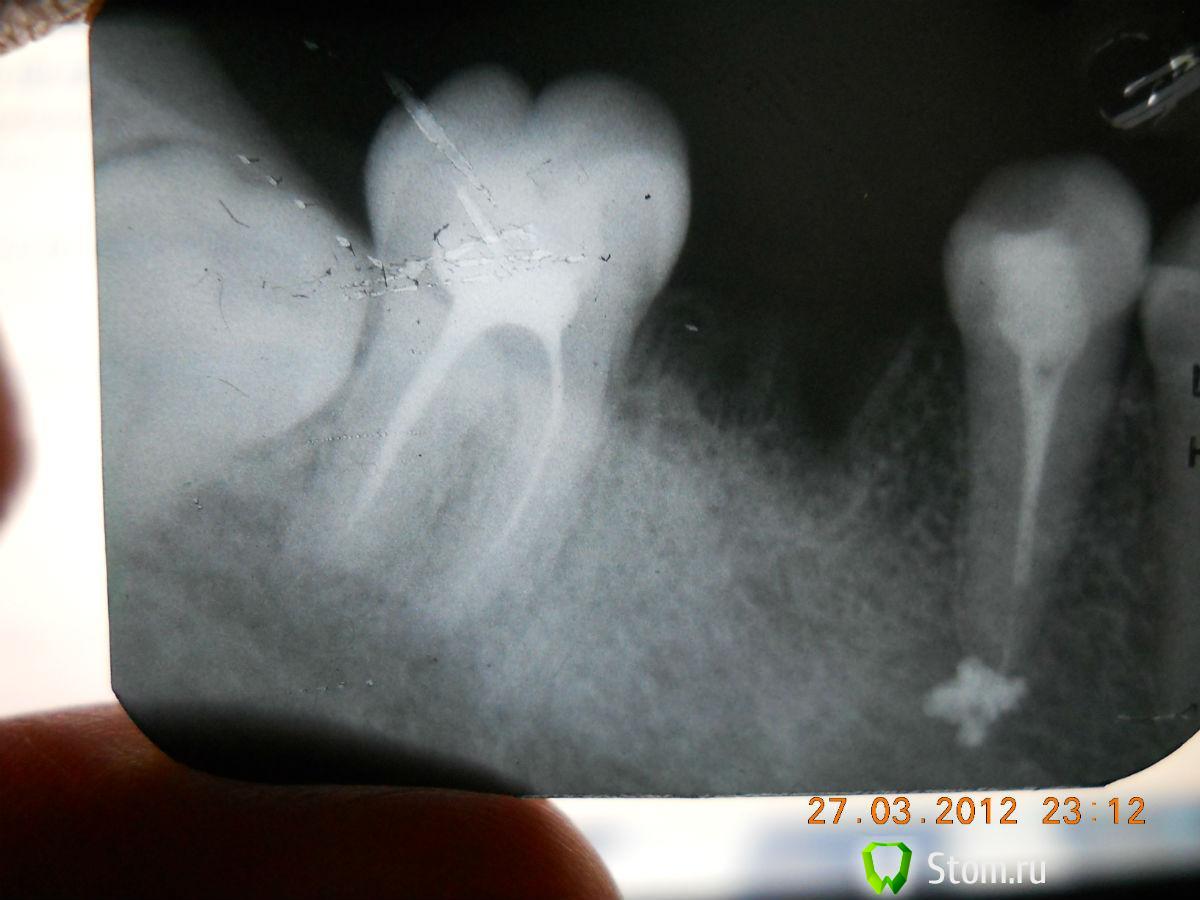

dok1 Опубликовано 26 марта, 2012 Поделиться Опубликовано 26 марта, 2012 На снимке 8 упирается в 7, пища забивается в любом случае, т.к. слизистая оболочка над 8 всего лишь охватывает стенку 7, а не прирощена к нему.Гигиена, какая бы не была идеальная, там бессильна.Бактериальная флора сделает своё дело - кариес ниже уровня десны - это приговор 7.А 7 ваша единственная дальняя опора мостовидного протеза.8 просто необходимо убрать.А теперь ответьте себе на вопрос: на что вы готовы пойти ради сохранения 7-ки на максимально долгий срок, если имплантация для вас неприемлема?Из личного опыта: пока пациенту не выложешь правду, какая она есть - сознание не включится. Любите себя, цените своё здоровье.Оно никому кроме вас не нужно.Удачи. Ссылка на комментарий

JOY Опубликовано 27 марта, 2012 Автор Поделиться Опубликовано 27 марта, 2012 Сегодня снова повторила снимок депульпированного 7 зуба.. Мой врач не видит никакой гранулемы... Ссылка на комментарий

Ayrat_zub Опубликовано 27 марта, 2012 Поделиться Опубликовано 27 марта, 2012 (изменено) Сегодня снова повторила снимок депульпированного 7 зуба.. Мой врач не видит никакой гранулемы...вам уже не раз написали, но...1.в любом случае каналы стоит перелечить, они недопломбированы2. конструкция, которую по плану решено водрузить на ваши зубы, скорее всего, в скором времени приведет к их удалению(из -за прегрузки опор) Изменено 27 марта, 2012 пользователем Ayrat_zub Ссылка на комментарий

Bier Опубликовано 28 марта, 2012 Поделиться Опубликовано 28 марта, 2012 гранулема там таки есть, если ваш врач её не видит, то можете сделать КТ, там точно будет видно. канал в вашем 5м зубе запломбирован не очень... ну и в 7м тоже. Ссылка на комментарий